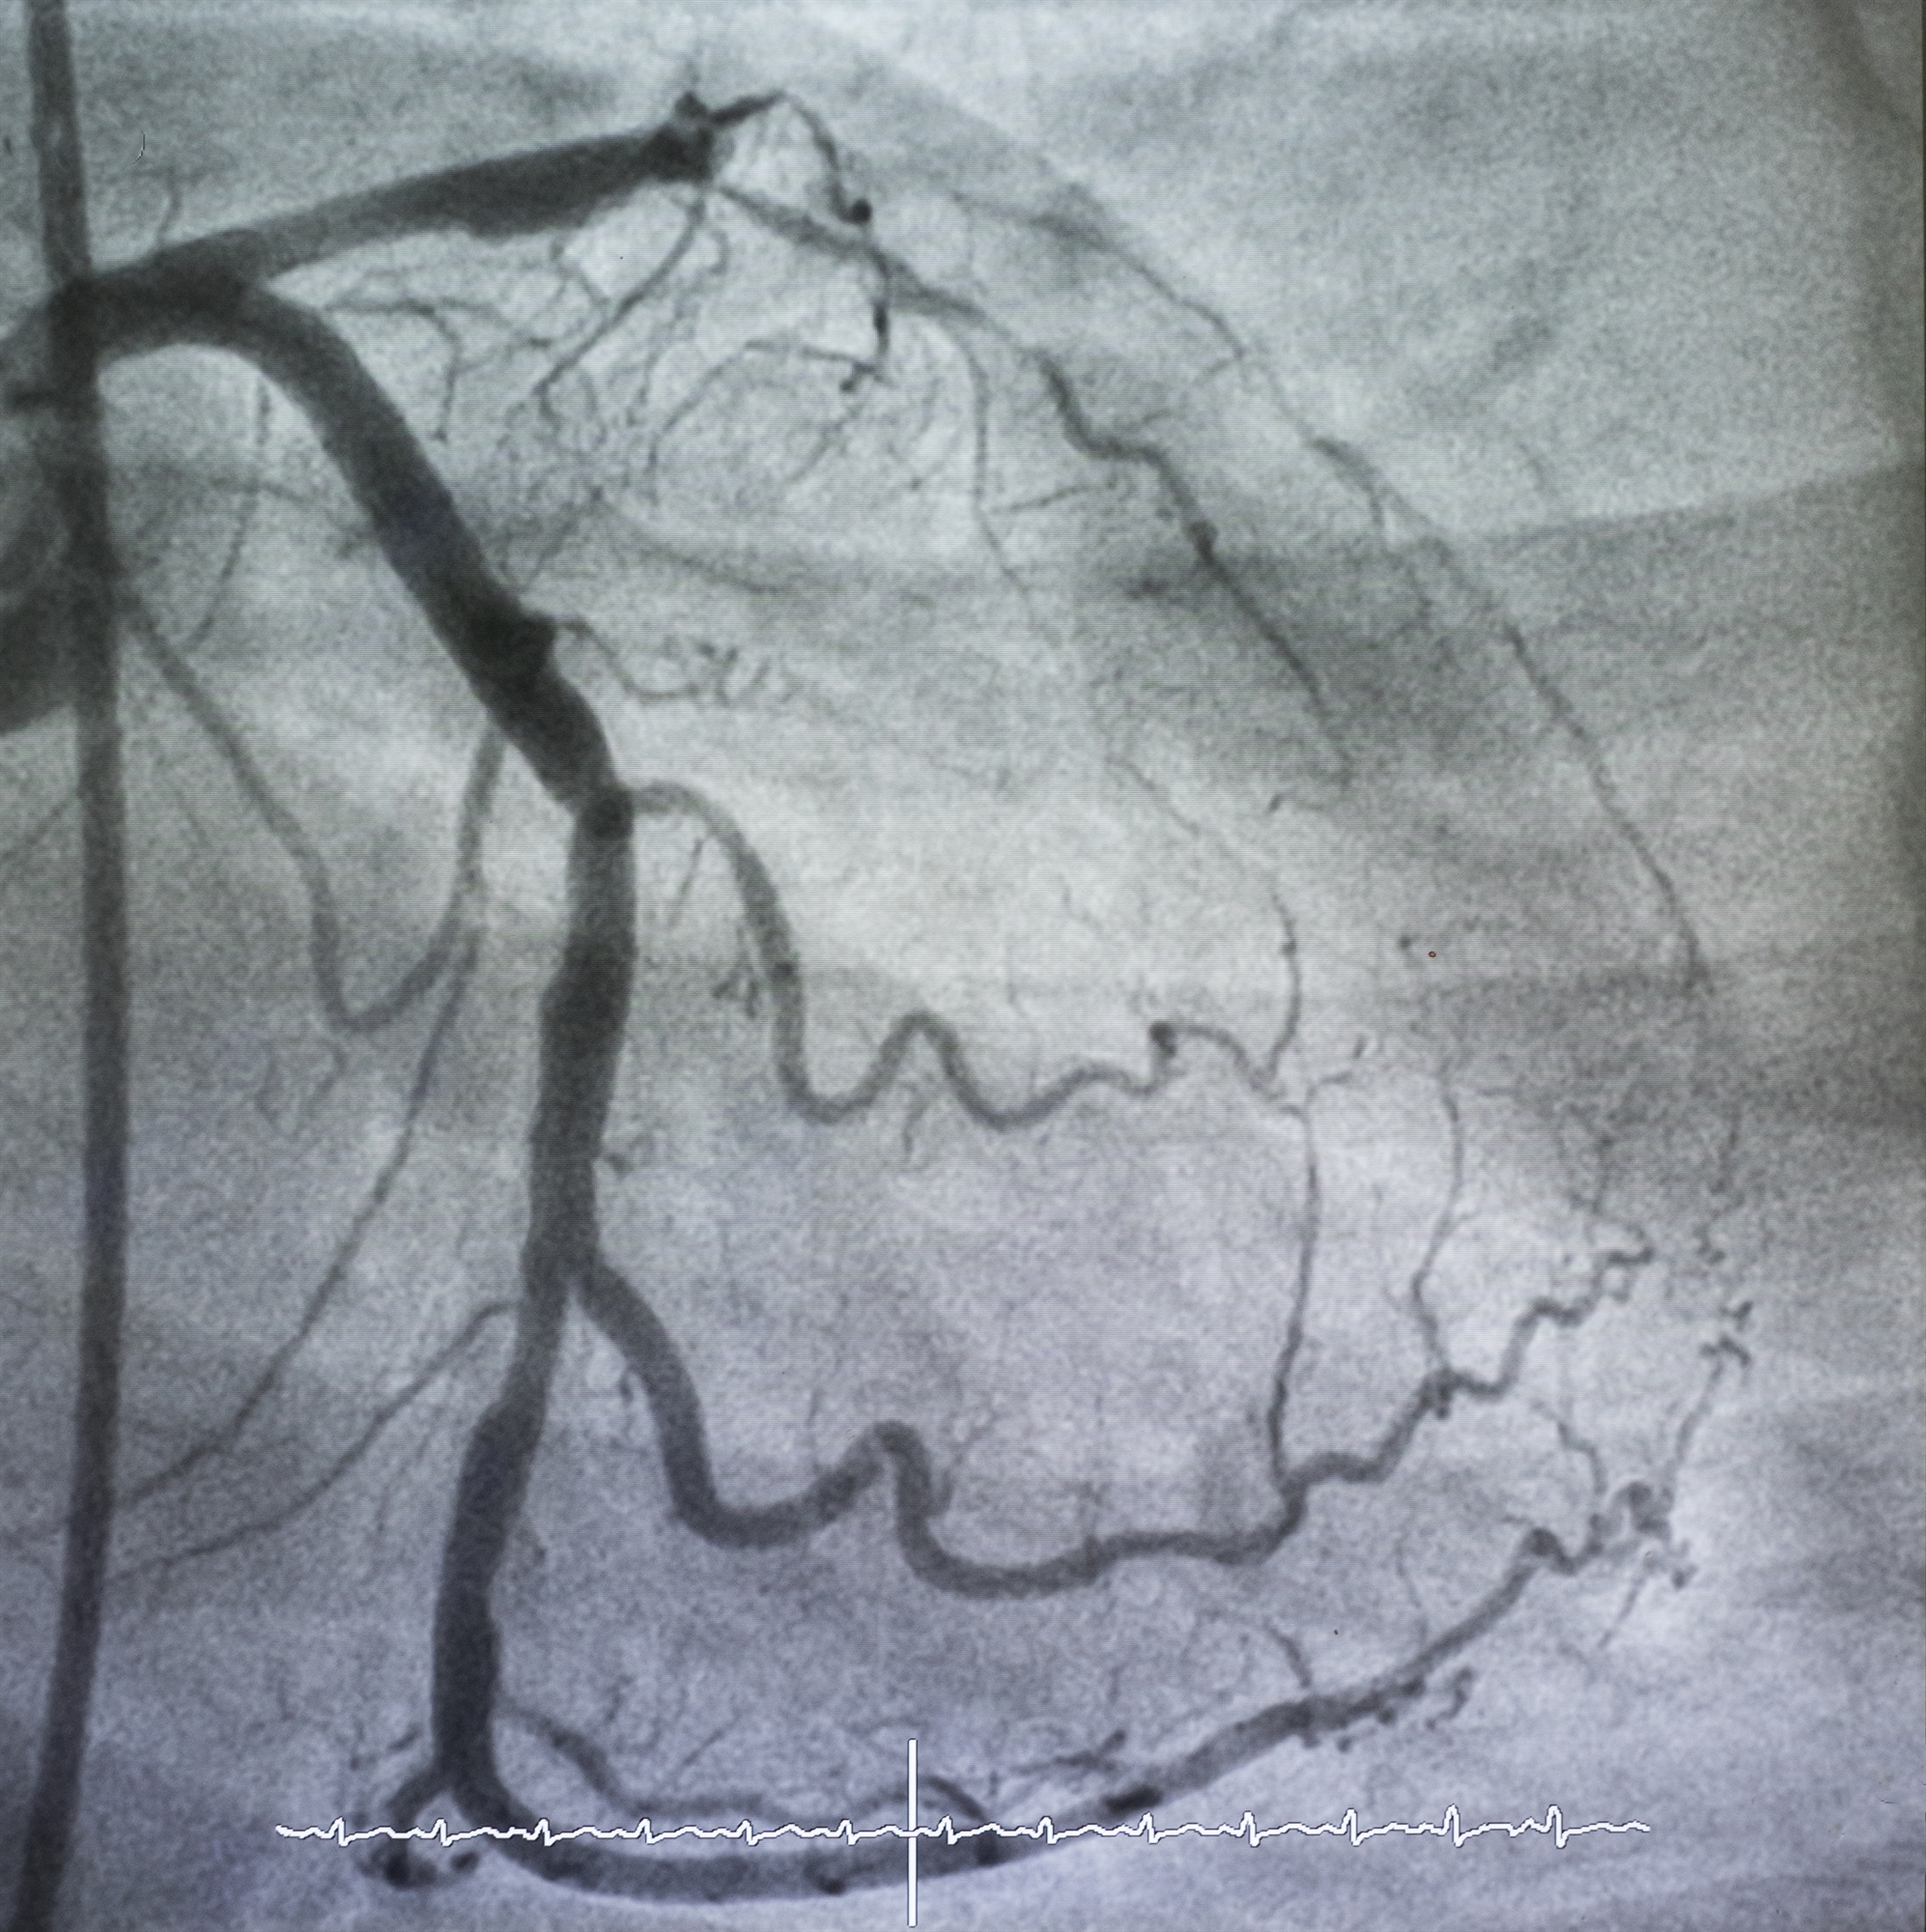

Στεφανιαία μικροαγγειακή δυσλειτουργία: προβλήματα από τα μικροσκοπικά αγγεία

Χάρη στην όλο και μεγαλύτερη χρήση εξειδικευμένων διαγνωστικών εργαλείων, αυτή η συχνά κρυμμένη πάθηση καθίσταται ευρύτερα αναγνωρίσιμη.